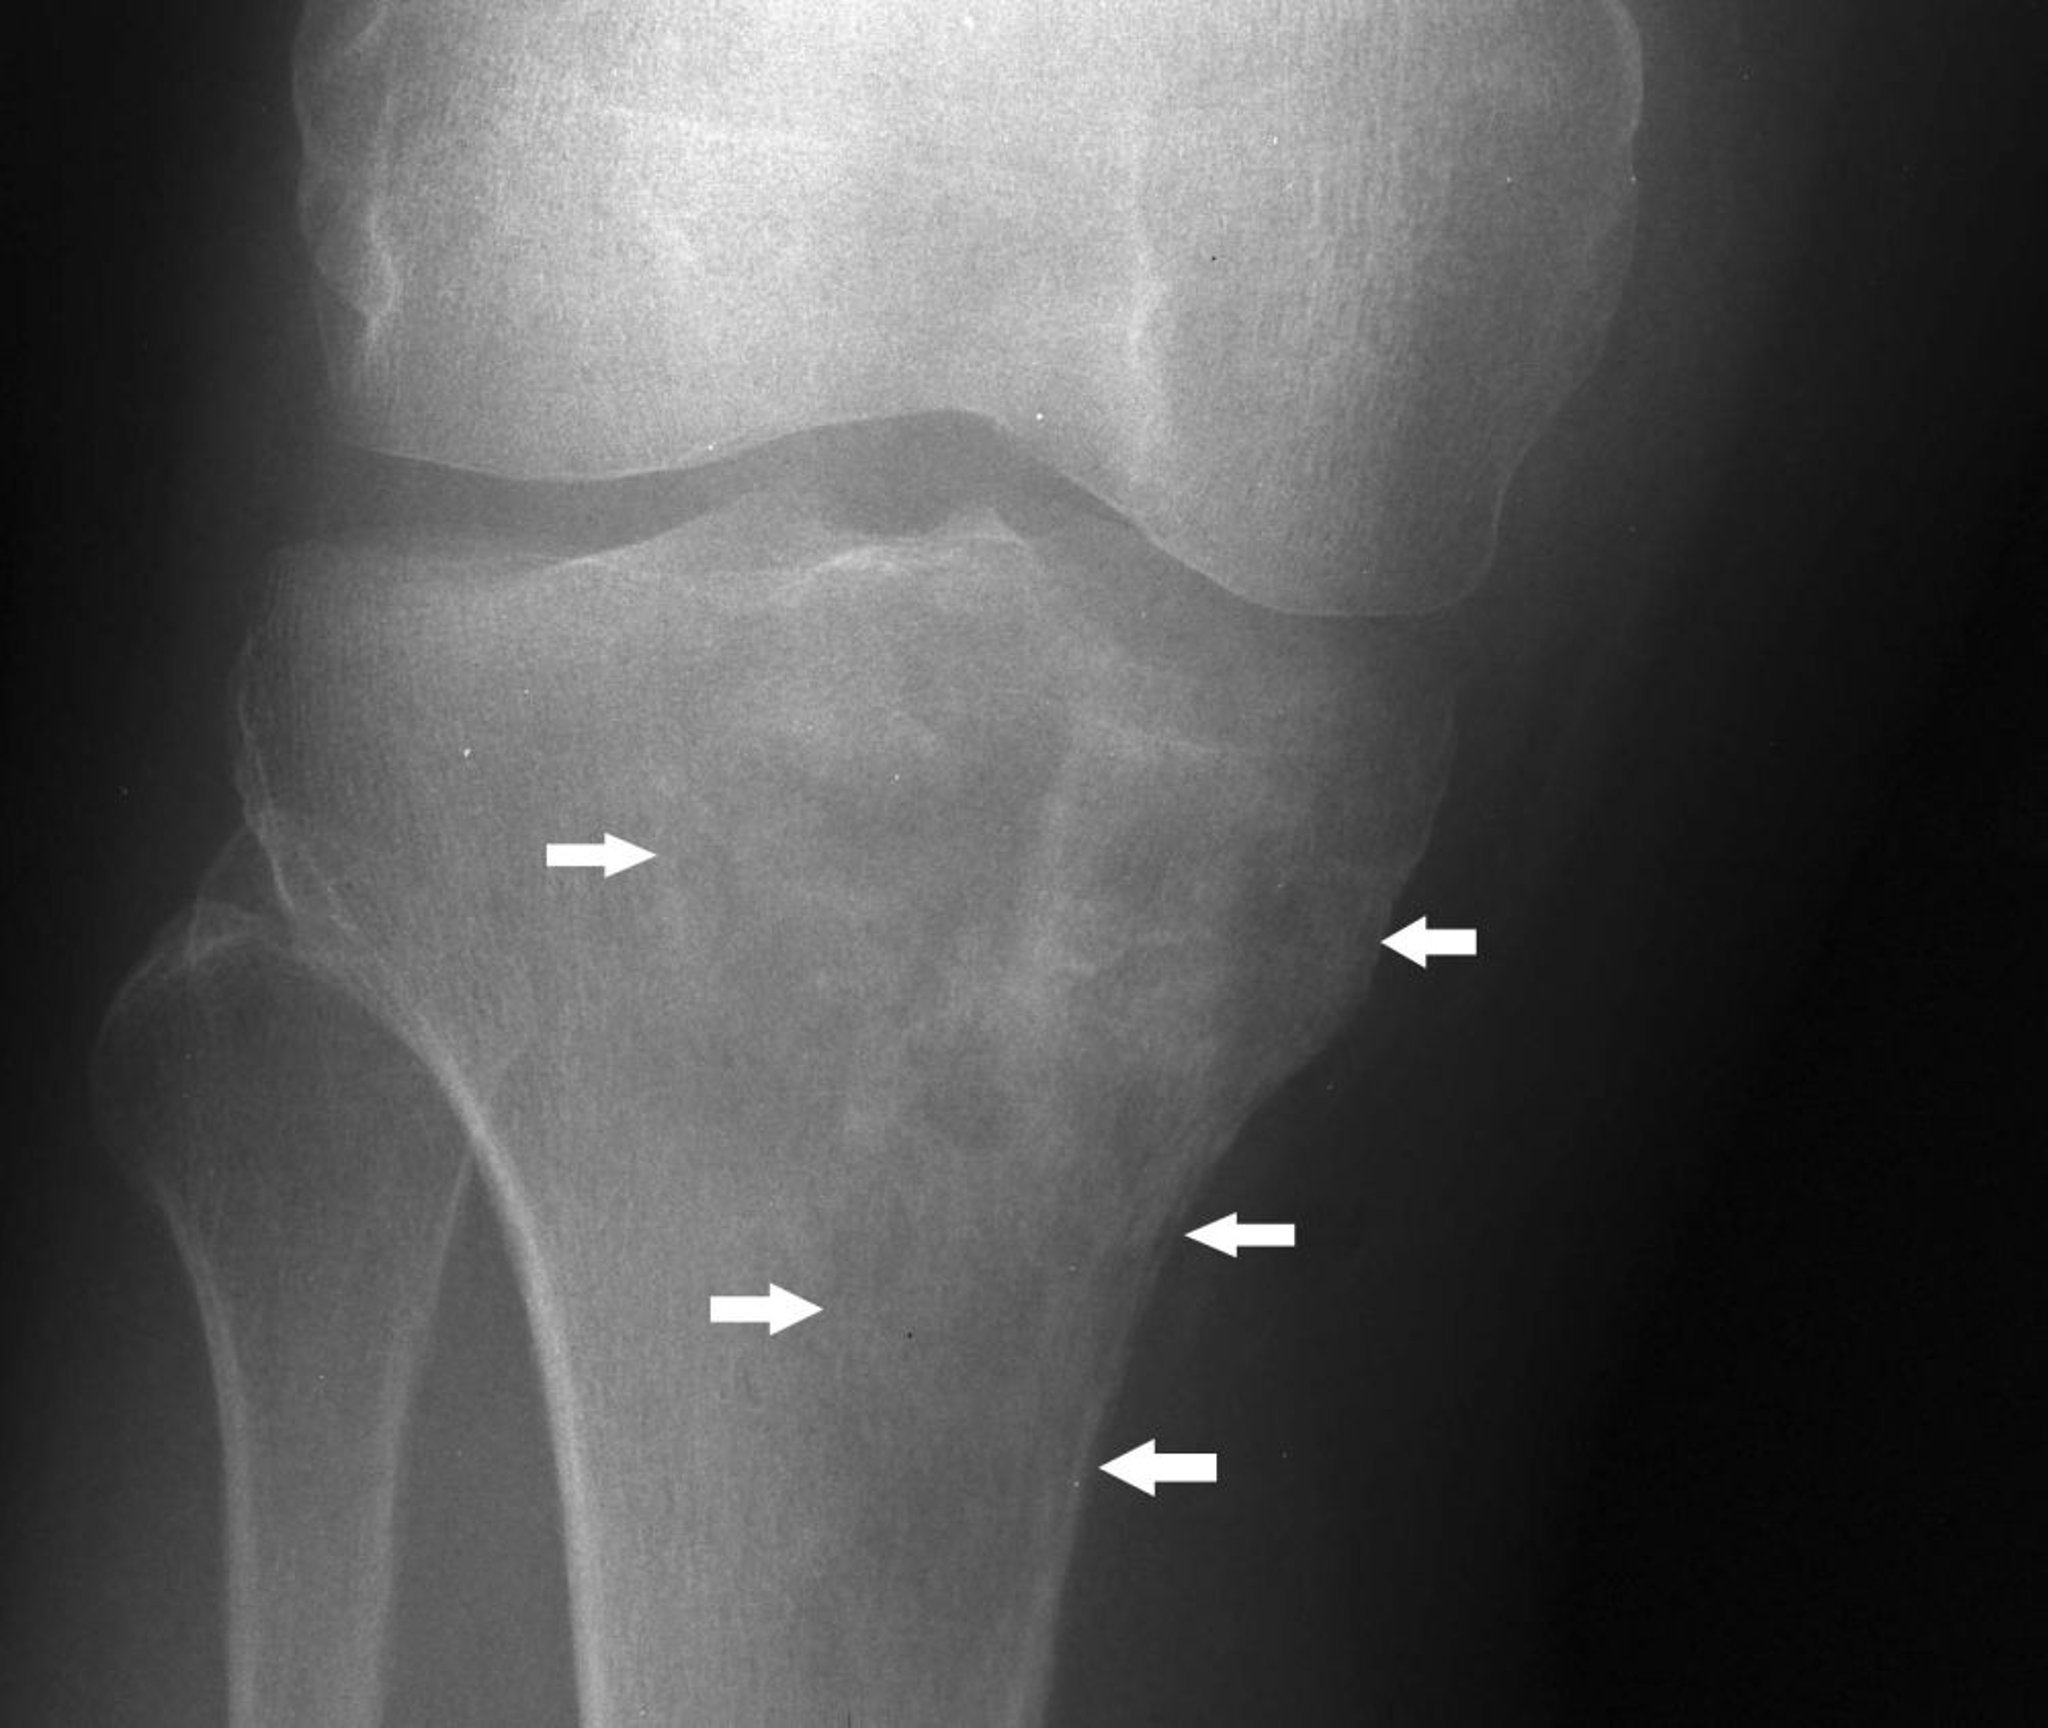

Лимфома кости

На данном рентгеновском снимке колена показана лимфома в проксимальной части большеберцовой кости со смешанным литическим и склеротическим проявлением ниже медиального мыщелка большеберцовой кости (стрелки).

Image courtesy of Michael J. Joyce, MD, and Hakan Ilaslan, MD.